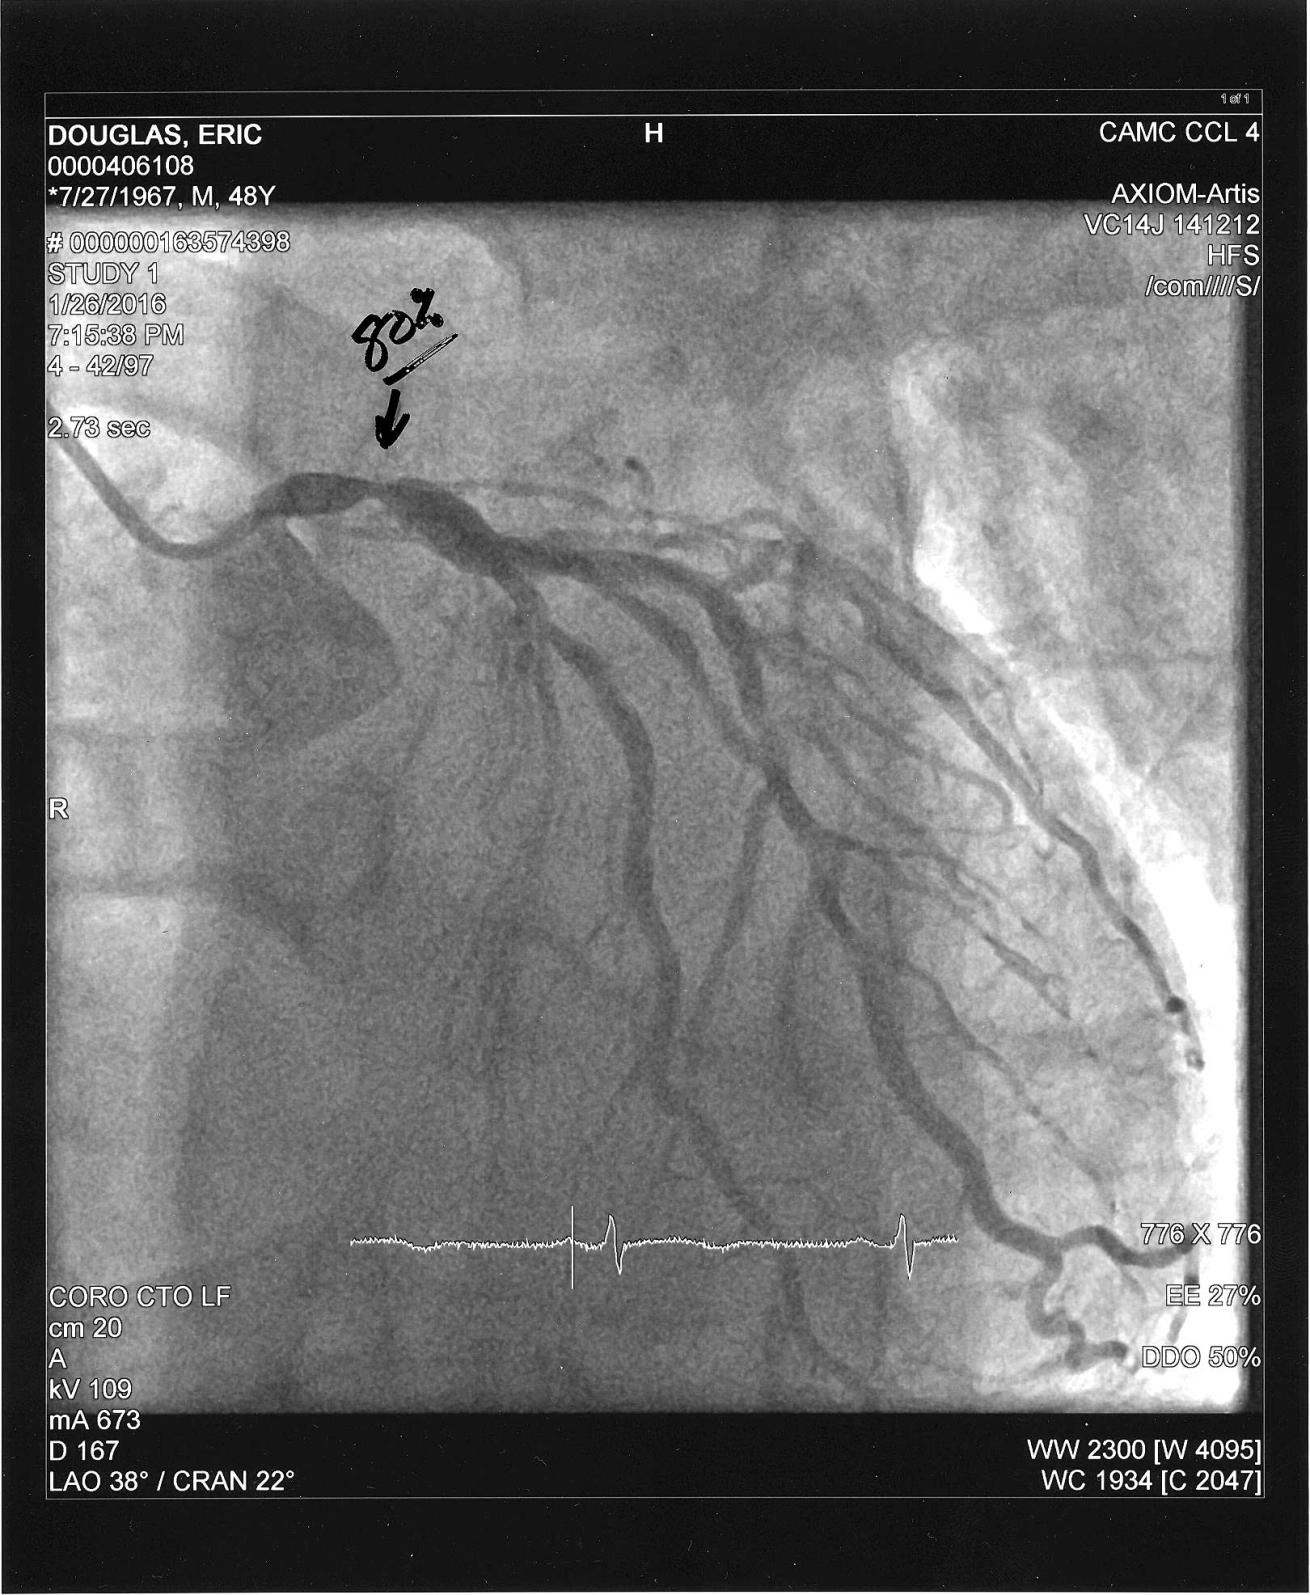

Courtesy Eric DouglasA picture of the heart catheterization that revealed blockages and restrictions in the author's coronary arteries requiring bypass grafts.

Courtesy Eric DouglasAnother heart catheterization from Douglas: This image shows an 80-percent-blocked artery.

This particular explanation was interesting to me. I had a heart attack, but didn’t realize what was actually happening at the time. I wrote about that in the first Heart Disease and Diving column. It wasn’t until my cardiologist gave me a heart catheterization that I actually knew that I’d had a heart attack. As I understand it, my heart muscle showed some signs of injury, but it wasn’t severe enough that it caused any worry. They had seen worse and felt that once they restored normal blood flow to my heart muscle, it should heal and return to normal function. That was good news for me and diving: I wouldn’t have been able to get back at it if my heart wasn’t pumping at full capacity.